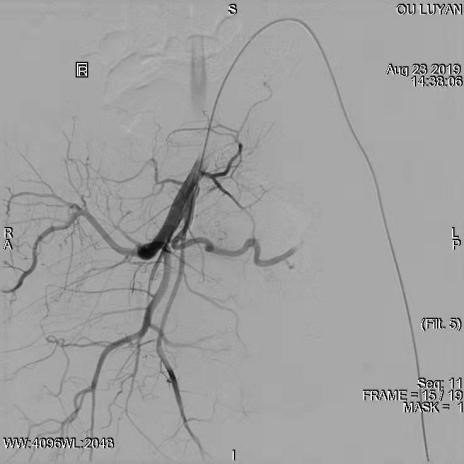

综合评估后考虑患者为Ⅱ型子宫切口妊娠,与患者及家属沟通后决定选择药物杀胚同时行双侧子宫动脉栓塞术。DSA显示双侧子宫动脉增粗、迂曲,均注入150-560um明胶海绵颗粒,造影显示栓塞满意。血β一HCG下降后在宫腔镜、B超引导下清除妊娠病灶,积极终妊。8月27日,手术过程进行顺利,未输血,患者于9月1日出院,后期继续加强康复治疗,预防远期并发症宫腔粘连发生。

左侧子宫动脉增粗、迂曲

栓塞术后左侧子宫动脉未见显影